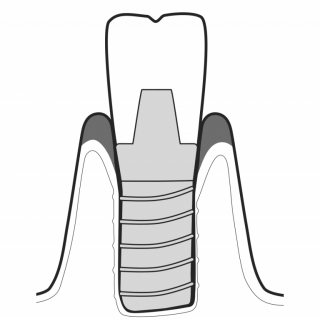

TREAT MUCOSITIS

While gentle on peri-implant tissues, AIRFLOW® with PLUS Powder safely reaches and cleans any ruggedness on implant surfaces for optimum biofilm removal. GBT is the state-of-the-art approach to implant maintenance.

TREAT PERI-IMPLANTITIS

PERIOFLOW® with PLUS Powder removes subgingival biofilm with unequalled limitation of peri-implant bleeding.The PIEZON® PI Instrument removes the remaining abutment calculus thereby preserving the implant surface.